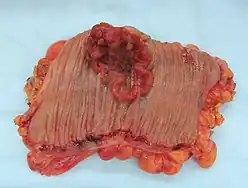

Cáncer colorrectal

Beber puede ser una causa de la aparición más temprana del cáncer colorrectal.[58] La evidencia de que el alcohol es una causa de cáncer de colon es convincente en los hombres y probable en las mujeres.[59]

Los Institutos Nacionales de Salud,[60] el Instituto Nacional del Cáncer,[61] Investigación del Cáncer,[62] la Sociedad Americana del Cáncer,[63] la Clínica Mayo,[64] y la Coalición del Cáncer Colorrectal,[65] la Sociedad Americana de Clinical Oncology[66] y el Memorial Sloan-Kettering Cancer Center[67] enumeran el alcohol como un factor de riesgo.

Un informe del grupo de expertos del WCRF considera "convincentes" las pruebas de que las bebidas alcohólicas aumentan el riesgo de cáncer colorrectal en los hombres en niveles de consumo superiores a 30 gramos diarios de alcohol absoluto.[68] El Instituto Nacional del Cáncer afirma: "El consumo excesivo de alcohol también puede aumentar el riesgo de cáncer colorrectal".[69]

Un metanálisis de 2011 encontró que el consumo de alcohol estaba asociado con un mayor riesgo de cáncer colorrectal.[70]